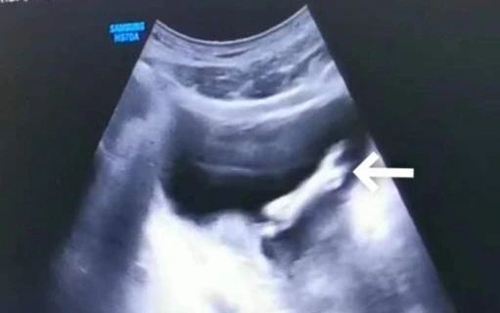

經(jīng)過查體,接診專家發(fā)現(xiàn)明明陰莖根部能摸到膠皮管樣物,超聲檢查結(jié)果顯示膀胱內(nèi)也有盤曲扭轉(zhuǎn)的膠皮管,診斷為膀胱及尿道異物。

超聲下膠皮管膀胱內(nèi)段